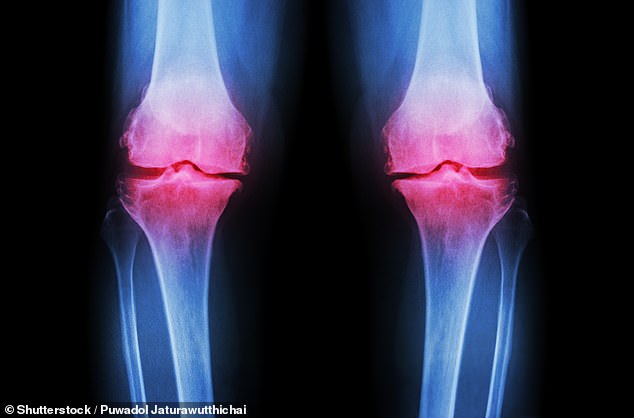

Osteoarthritis occurs when protective cartilage erodes, leading to joint pain and stiffness. While factors like genetics, obesity, and injury contribute, the role of high-impact fitness and poor nutrition is becoming clear. Post-traumatic osteoarthritis, often linked to joint fractures, is on the rise, with improper healing altering joint mechanics and accelerating cartilage loss. Younger patients face a dual challenge: managing symptoms over decades and dealing with the social and economic impacts of chronic pain during peak productivity years.